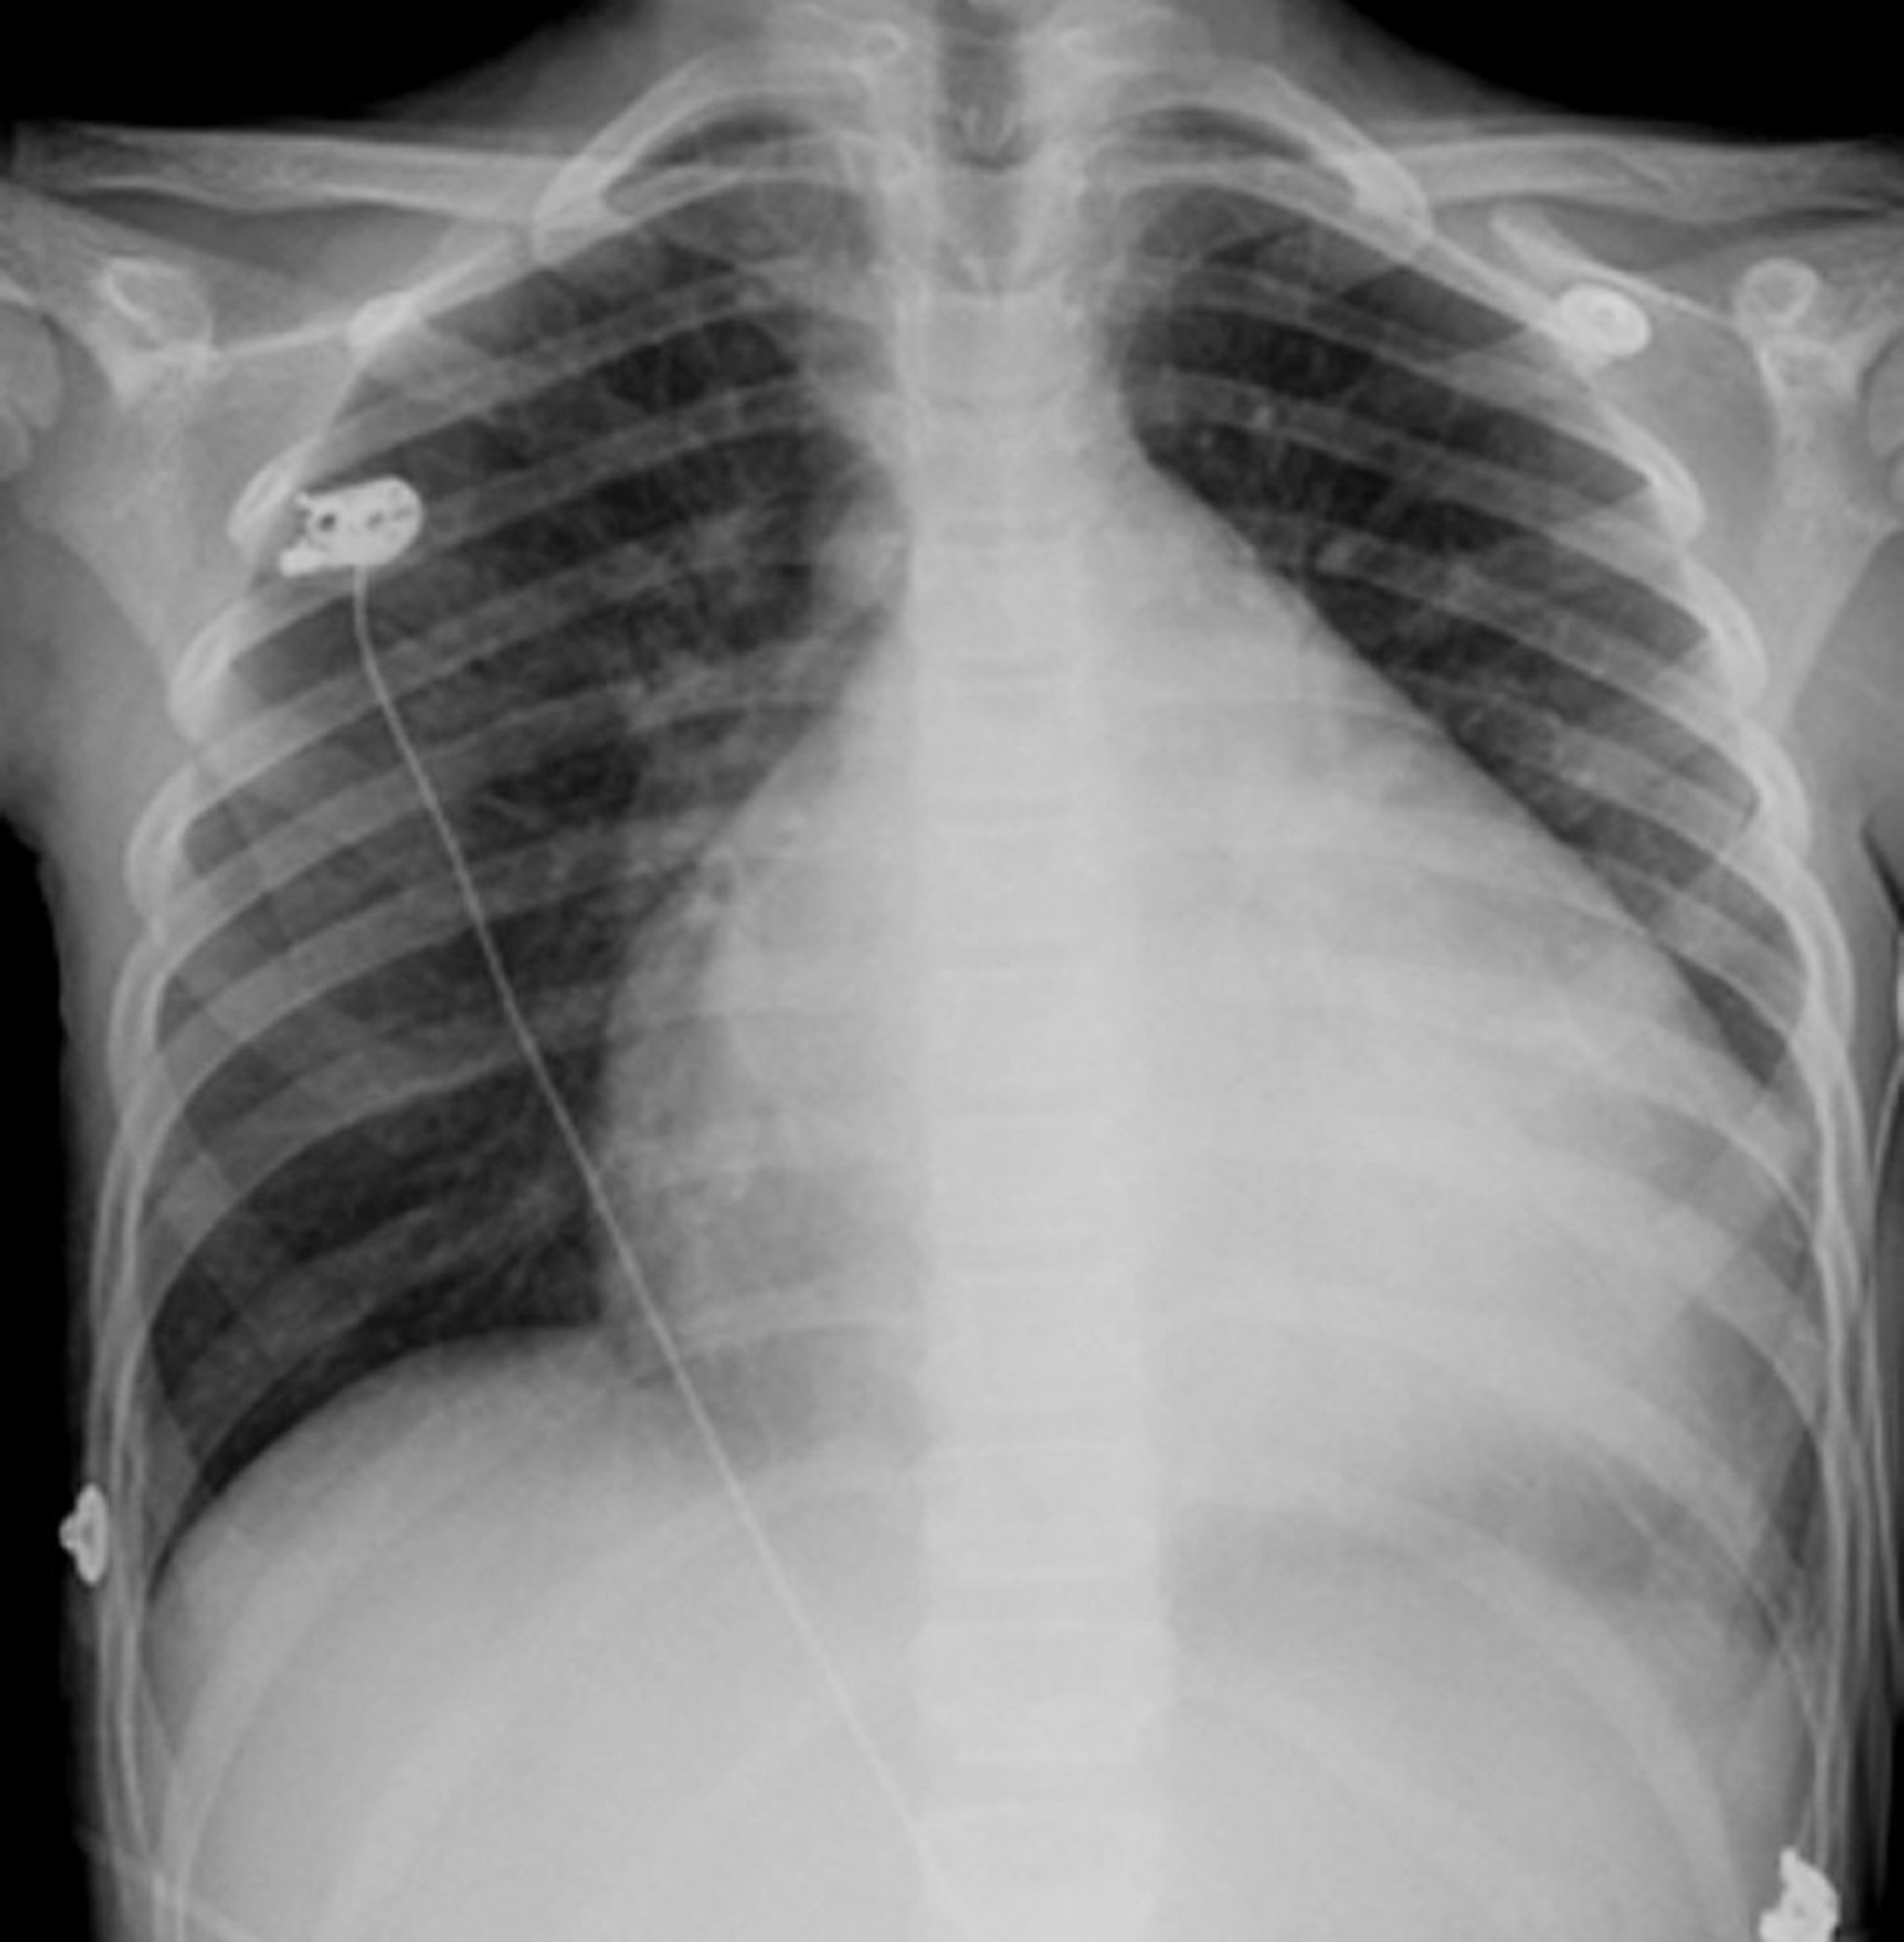

This x-ray shows severe cardiomegaly in a patient with dilated cardiomyopathy.